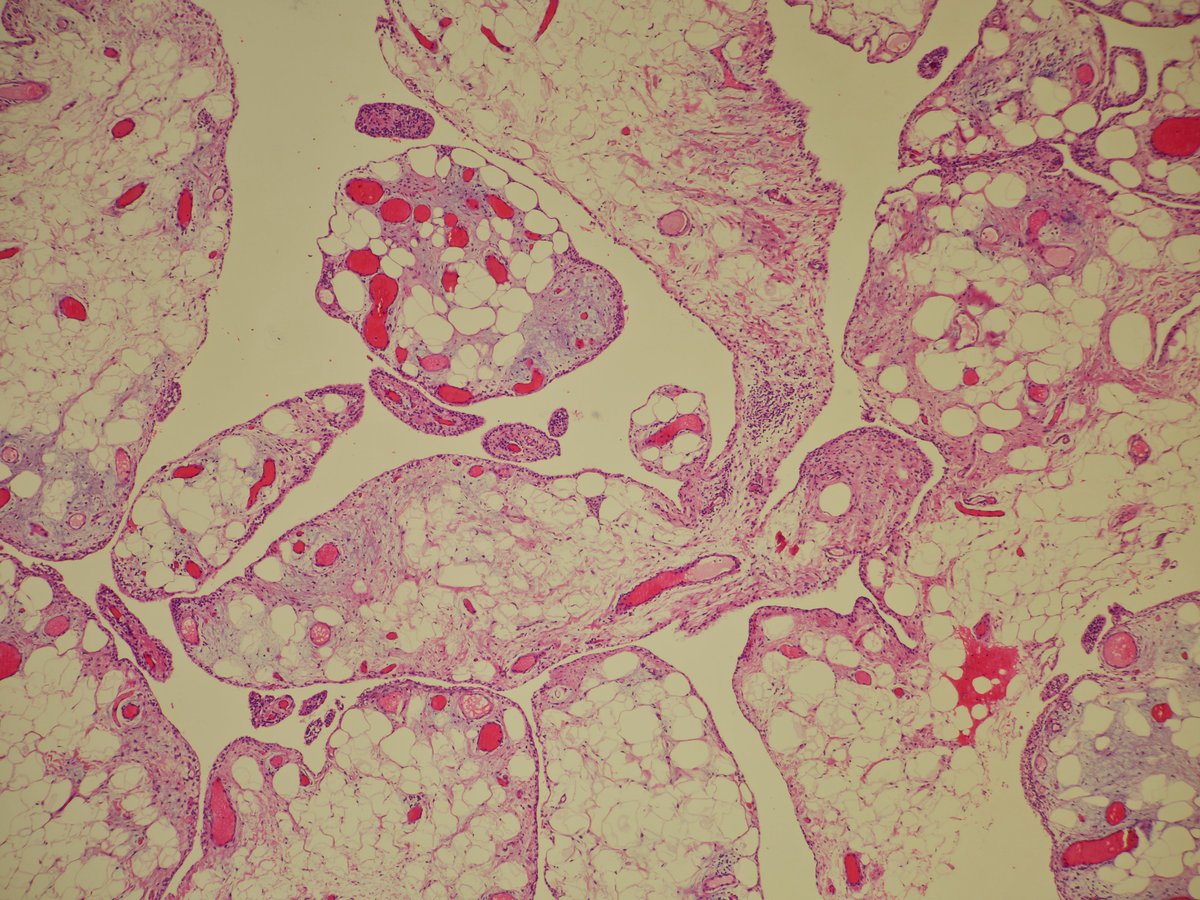

Synovial lipomatosis (lipoma arborescens, Hoffa's disease)

➡️Mature unremarkable fat extending to the partly hyperplastic synovial lining, imparting a villiform/papillary architecture

➡️Scattered chronic inflammation

➡️M>F, usually knee joint

#BSTPath #PathTwitter #pathoutpic